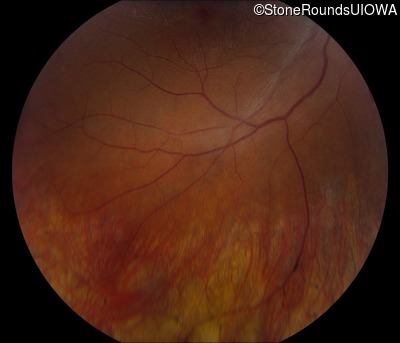

Fundus Photography - Left - 20/50 -3

Exemplar